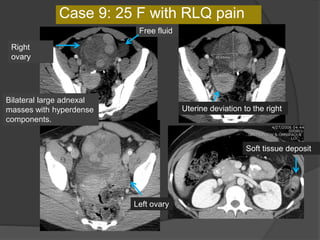

Bilateral large adnexal

masses with hyperdense

components.

Right

ovary

Left ovary

Free fluid

Uterine deviation to the right

Case 9: 25 F with RLQ pain

Soft tissue deposit

Dx: Bilateral struma ovarii with torsion of

the right ovary and benign strumosis

Take home points-

1. Consider the possibility of torsion in presence of a large adnexal

mass and appropriate clinical setting

2. Ascites , abnormal location of the ovary, ipsilateral deviation of the

uterus indicate adnexal torsion

Struma ovarii

 Struma ovarii is composed predominantly of thyroid

tissue. It accounts for approximately 3% of all mature

cystic teratomas

 US and CT demonstrate its complex appearance

with multiple cystic and solid areas. When struma

ovarii is not associated with hyperthyroidism, the

differential diagnosis should include mature cystic

teratoma without fatty tissue, cystadenoma or

cystadenocarcinoma, endometriosis, tuboovarian

abscess, and metastatic tumor

 Malignant transformation of thyroid tissue in struma

ovarii and metastasis are extremely uncommon

 In rare cases, benign thyroid tissue may spread to

the peritoneal cavity. This condition is termed

"peritoneal strumosis."